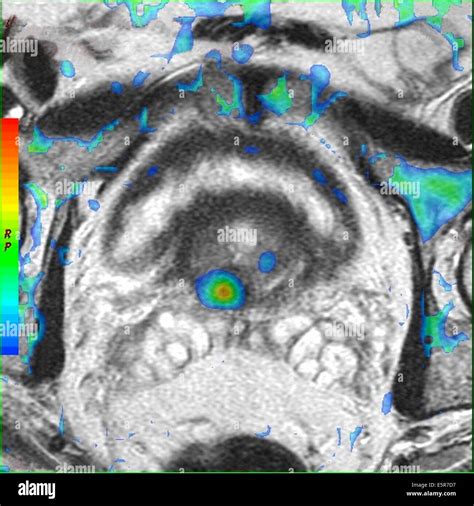

• Dynamic contrast-enhanced (DCE) MRI: Uses a contrast agent to assess blood flow and vascularity within the prostate, helping to identify areas of increased blood flow that may be associated with cancer.

• Functional MRI: Functional MRI techniques, such as diffusion-weighted imaging and dynamic contrast-enhanced MRI, provide additional information about the metabolic and vascular characteristics of prostate tumors. This can help to differentiate between benign and malignant lesions.